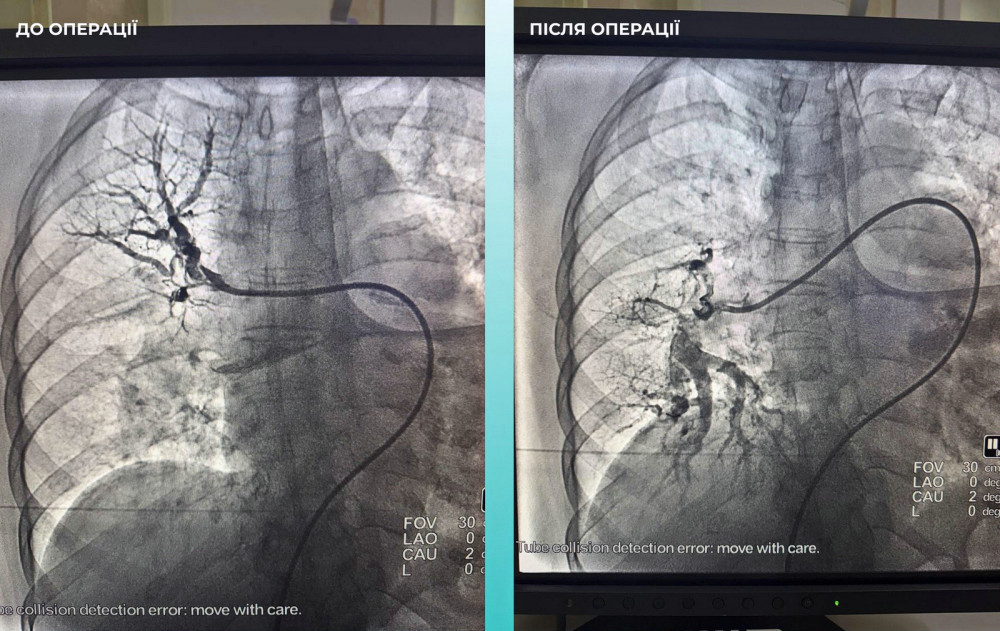

Команда фахівців прийняла важливе рішення провести одночасну тромбектомію мозкових та легеневих артерій.

Операція була успішною. Наразі пацієнтка почуває себе значно краще: вона в свідомості та може рухати кінцівками.